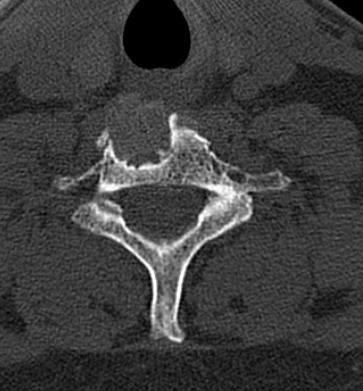

Obsérvese la ubicación de la prótesis